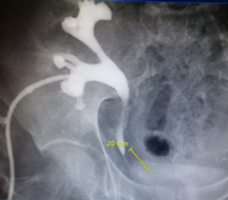

Пациентка 60 лет длительно страдала поликистозом обеих почек, который привел к развитию терминальной почечной недостаточности и утрате функций обеих почек. В 2013 году почки были удалены, в течение 3-х лет пациентка получала лечение программным гемодиализом, и в феврале 2016 года ей была выполнена пересадка донорской почки. Но уже в мае 2016 года пациентка поступила в отделение урологии ГКБ № 52 с острой почечной недостаточностью на фоне обструкции (непроходимости) верхних мочевых путей по причине 2-х сантиметровой стриктуры (сужения) в нижней трети донорского мочеточника (рис. 1) .